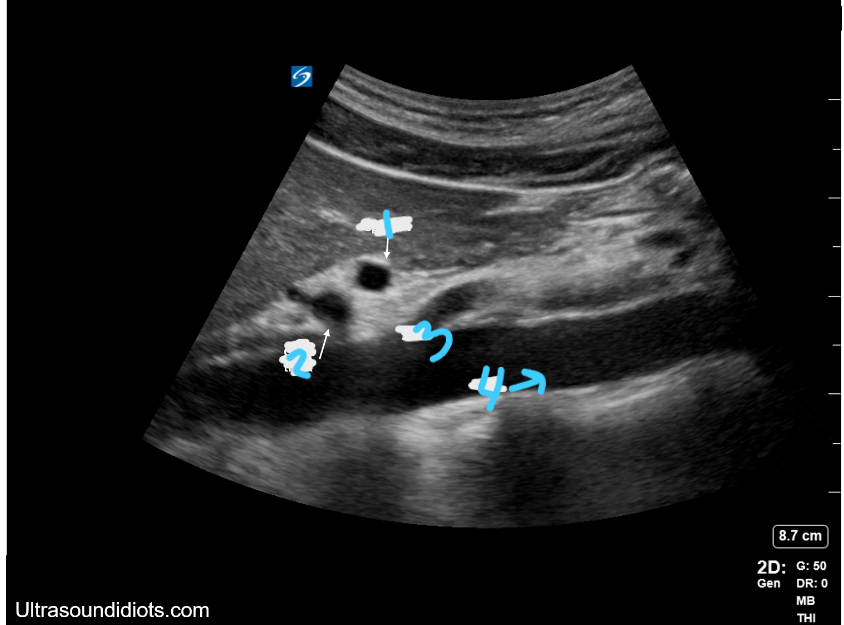

<p>In this Sagittal view, what is #1?</p>

In this Sagittal view, what is #1?

Celiac Trunk

<p>In this Sagittal view, what is #2?</p>

In this Sagittal view, what is #2?

SMA

<p>In this Sagittal view, what is #3?</p>

In this Sagittal view, what is #3?

Aorta

<p>What is this structure in this the picture?</p>

What is this structure in this the picture?

<p>What is this structure?</p>

What is this structure?

Aorta with the SMA coming off the top